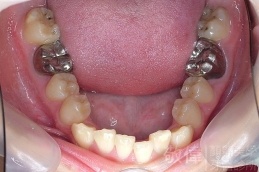

變臉矯正,原來戽斗妹跟大歪臉變成自信正妹

經由本院3D數影X光影像儀分析、與3D齒顎顏矯正技術,再配合口腔顎面正顎專科醫師施以正顎手術治療,雙方共同合作,使患者臉部外觀有很好的改善,大歪變小歪,產生了天南地北的大改變,她的人生也整個變得不一樣。

因為矯正與正顎手術的配合,使「戽斗妹」變成了「陽光正妹」,完全的改變了她的人生,在面對各種場合、與人交際都散發出自信微笑。所以,奉勸家長,如果小朋友有臉顎畸型的問題,應該考慮配合做這種簡單、安全、有效的正顎手術。